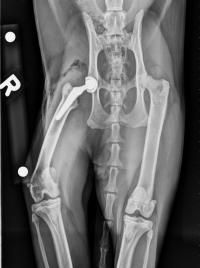

A 2-year-old male cheetoh cat (Bengal/ocicat cross) named Atlas came to the University of California, Davis School of Veterinary Medicine after a jumping accident left him lame. The Orthopedic Surgery Service at the UC Davis veterinary hospital took x-rays of Atlas, finding a displaced fracture of the right femoral head that would need surgery. After discussing the options with owners Sheila Dukas-Janakos and Ross Hite, Atlas received a total hip replacement, which utilizes a stem implant placed in the femur topped with a ball joint that interacts with a cup implanted in his pelvis.1

Total hip replacement is a procedure that is relatively new on cats, as there is limited research on the long-term effects. UC Davis was confident in this route for Atlas because the studies that have been done have shown positive outcomes. The university surgeons utilized a 3D computer assisted design planning system to aid them in the surgery. After a successful surgery, Atlas was hospitalized for a month to monitor his recovery. Once he was cleared to return home, he was placed back on strict cage rest for 2 more months.1

Three months post-operation, x-rays of Atlas showed success with the implant remaining in a stable position, and the cat’s gait was normal without noticeable lameness. Four months post-op and Atlas was allowed to slowly return to normal activity. The most recent update from Atlas’s owners came 8 months post-surgery and they reported that their cat is 100% recovered with no restrictions to his normal activities.1